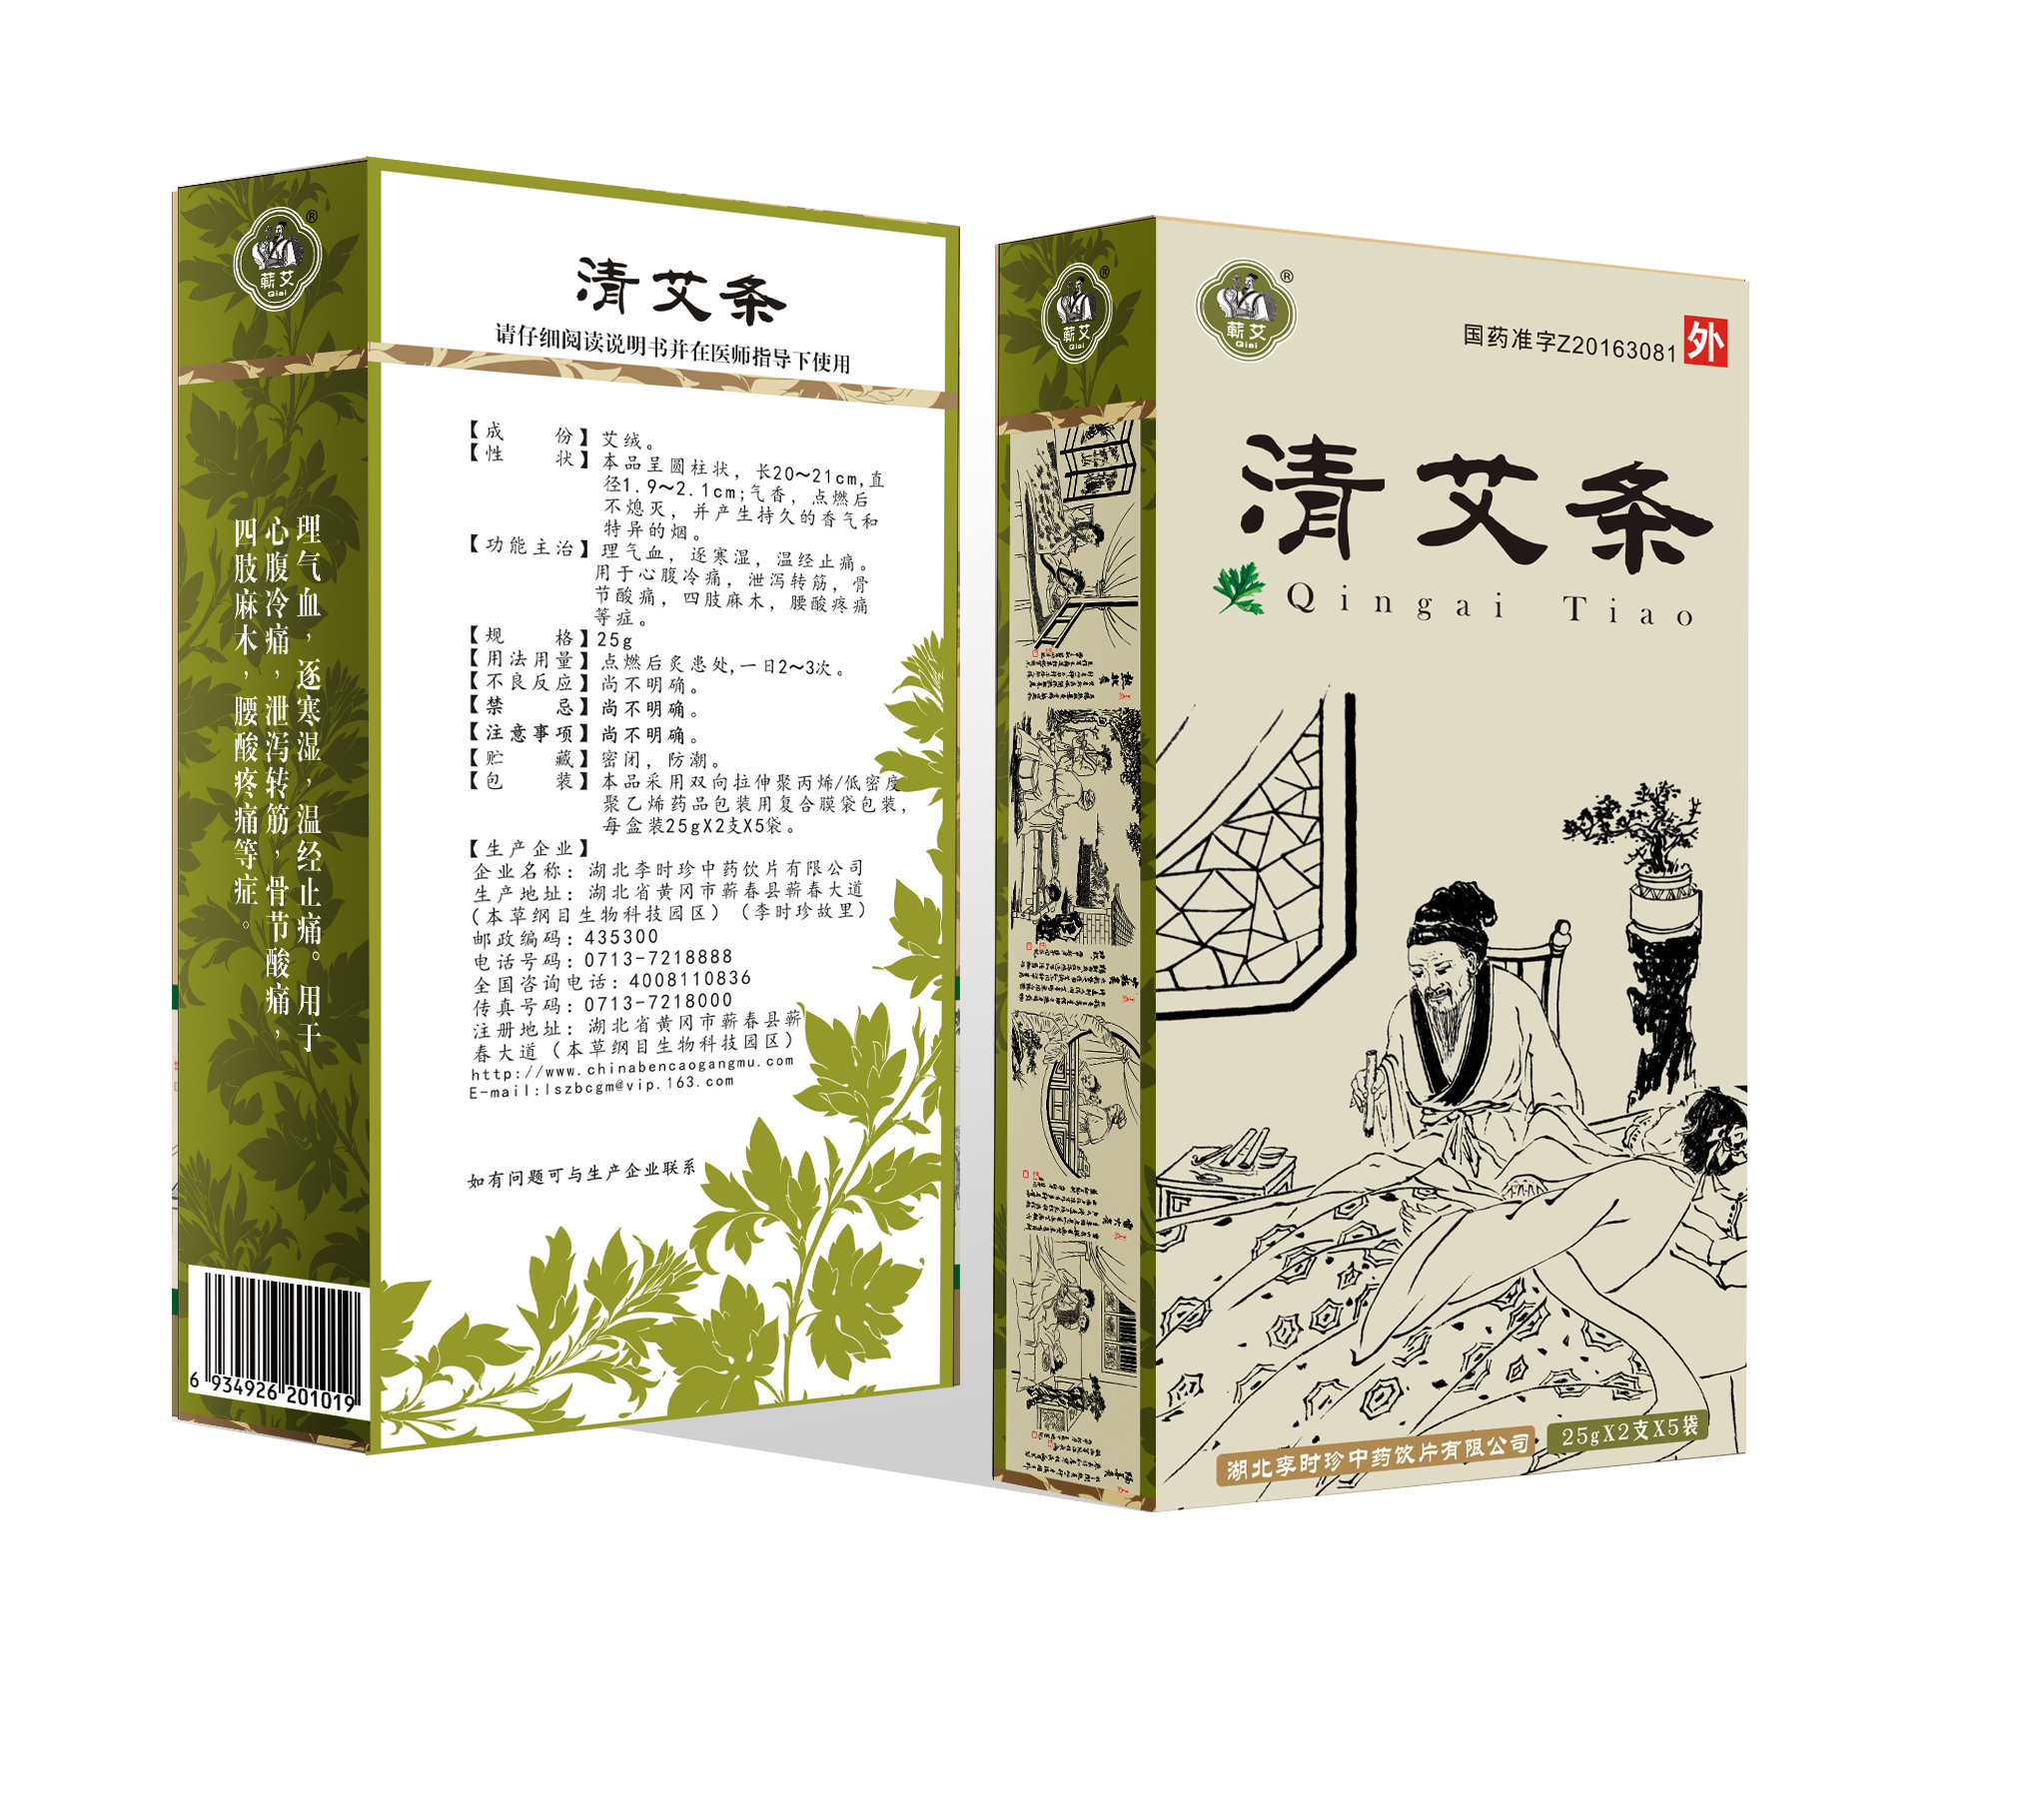

“传时珍医药伟业,谱本草科学新篇”,医药集团致力为广大用户提供一系列高质量的产品,涵盖了中成药、中药饮片、中药配方颗粒、保健酒、蕲艾系列大健康产品生产以及子公司厦门美商医药的化药。我们的产品结合了传统中医药炮制与现代科学技术,为用户提供健康、安全和有效的医药保健解决方案。 医药集团主要生产中成药品种近100个,其中40余个基药品种可纳入医保目录。此外,集团还生产中药配方颗粒品种350余个,中药饮片品种700余个,以及蕲艾制品100余个。这些产品经过多次的GMP认证,保证其质量和安全性。